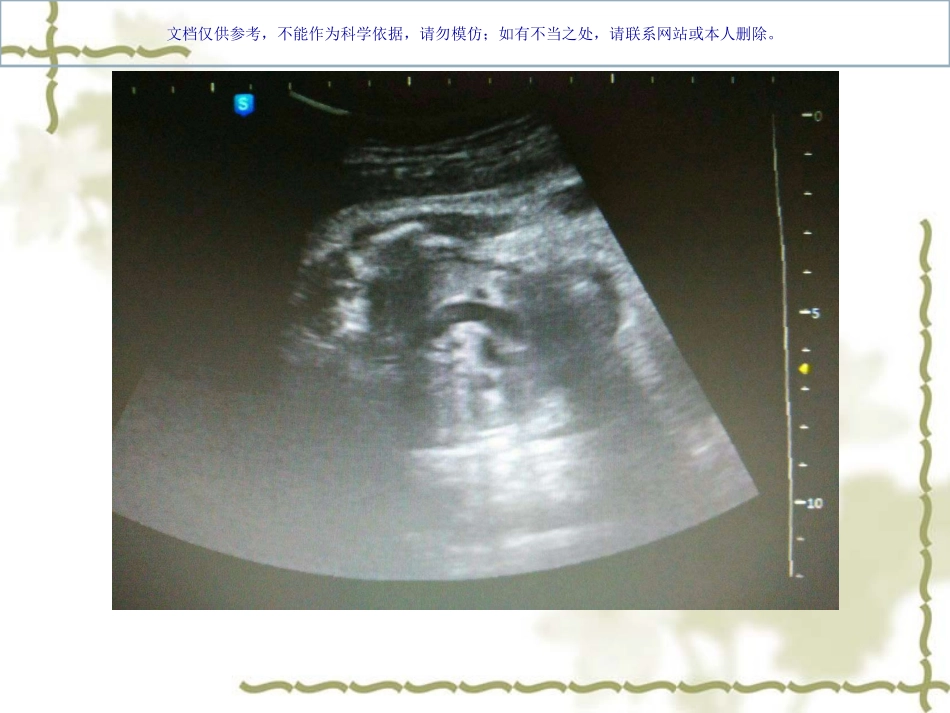

文档仅供参考,不能作为科学依据,请勿模仿;如有不当之处,请联系网站或本人删除。临床资料女27岁G1P0否认传染病及遗传病史孕30周常规产检胎儿超声检查三维及胎心检查未见异常其他实验室检查未诉异常文档仅供参考,不能作为科学依据,请勿模仿;如有不当之处,请联系网站或本人删除。文档仅供参考,不能作为科学依据,请勿模仿;如有不当之处,请联系网站或本人删除。文档仅供参考,不能作为科学依据,请勿模仿;如有不当之处,请联系网站或本人删除。文档仅供参考,不能作为科学依据,请勿模仿;如有不当之处,请联系网站或本人删除。文档仅供参考,不能作为科学依据,请勿模仿;如有不当之处,请联系网站或本人删除。永存左上腔?文档仅供参考,不能作为科学依据,请勿模仿;如有不当之处,请联系网站或本人删除。永存左上腔(PLSVC)是胎儿期最常见的先天性体循环静脉畸形正常人群中0.3-0.5%,先心中12%(畸形?变异?)文档仅供参考,不能作为科学依据,请勿模仿;如有不当之处,请联系网站或本人删除。胎儿静脉系统演变(部分)总主静脉:两侧总主静脉是胎儿最大的体静脉,右总主静脉发育形成上腔静脉,左总主静脉及其分支大部分蜕变(逐渐退化),部分残留形成冠状静脉窦。文档仅供参考,不能作为科学依据,请勿模仿;如有不当之处,请联系网站或本人删除。文档仅供参考,不能作为科学依据,请勿模仿;如有不当之处,请联系网站或本人删除。多数对血流动力学无影响,出生后无临床症状,少数?但这种畸形会增加心导管检查、起搏器植入及心脏外科手术的难度和风险。常合并心内外的畸形(内脏范围综合征)出生后常规心脏检查难以发现临床意义文档仅供参考,不能作为科学依据,请勿模仿;如有不当之处,请联系网站或本人删除。永存左上腔分型Ⅰ型:经冠状静脉窦引流入右心房(90%)Ⅱ型:经冠状静脉窦引流入右心房,但与左心房间有短路(部分右向左分流)Ⅲ型:直接引流入左心房Ⅳ型:冠状静脉窦闭锁,左上腔连接于左肺静脉文档仅供参考,不能作为科学依据,请勿模仿;如有不当之处,请联系网站或本人删除。文档仅供参考,不能作为科学依据,请勿模仿;如有不当之处,请联系网站或本人删除。超声检查常规胎儿心脏切面:腹部横切、四腔心切面、左右室流出道切面、三血管切面、主动脉弓切面、动脉导管弓及上、下静脉-心房连接切面(分型、孤立左上腔)四腔心切面:观察有无扩张的冠状静脉窦三血管切面:大血管的管径、数目、排列关系,观察肺动脉左侧血管是否有无,与扩张的冠状静脉窦相连文档仅供参考,不能作为科学依据,请勿模仿;如有不当之处,请联系网站或本人删除。文档仅供参考,不能作为科学依据,请勿模仿;如有不当之处,请联系网站或本人删除。文档仅供参考,不能作为科学依据,请勿模仿;如有不当之处,请联系网站或本人删除。文档仅供参考,不能作为科学依据,请勿模仿;如有不当之处,请联系网站或本人删除。文档仅供参考,不能作为科学依据,请勿模仿;如有不当之处,请联系网站或本人删除。临床意义Ⅰ型,无心内外畸形经左上肢行心导管检查时,不能进入右心房,进入冠状静脉窦(难度↑,放射线曝光时间延长)。起搏器植入。心外科手术建立体外循环时。Ⅱ、Ⅲ、Ⅳ型,右向左分流,不同程度的紫绀,需手术治疗合并其他心内、或心外畸形时(畸形?变异?)文档仅供参考,不能作为科学依据,请勿模仿;如有不当之处,请联系网站或本人删除。